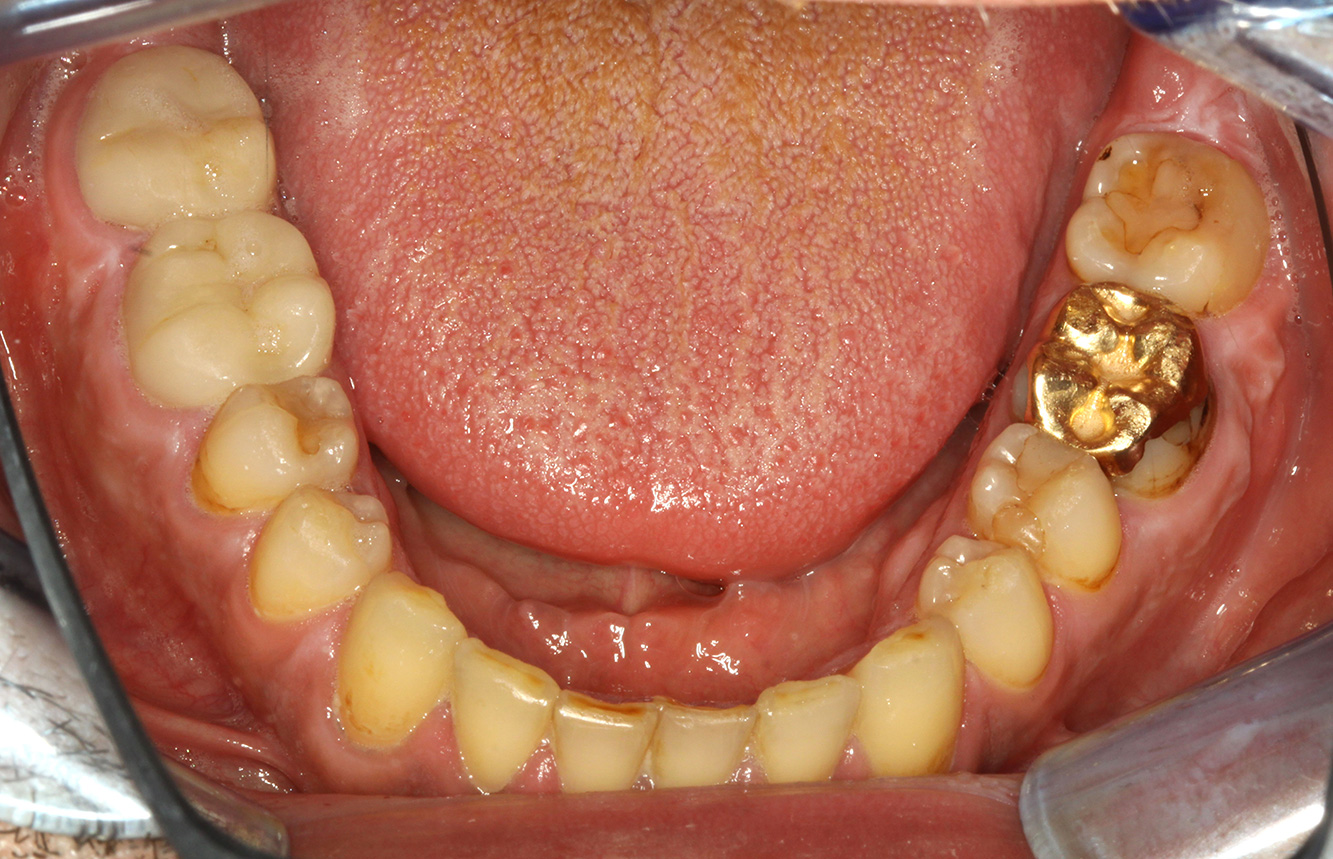

The endocarditis patient with active caries lesions*

The patient is 39 years old and has previously undergone aortic valve replacement due to valve failure and endocarditis. ASS 100 is taken regularly as an anticoagulant. In terms of lifestyle, the patient’s diet is classified as caries-promoting due to the regular consumption of sugary foods and the fact that six to seven meals are consumed daily. The patient’s oral health indicates a moderate risk of caries, with active lesions. The risk of periodontitis is low, but gingivitis is present. The following recommendations are made for prophylactic treatment.

No specific instrument recommendations can be determined for the prophylaxis session. Targeted application of air and rotary polishing can be used to gently reduce plaque and stains on the restoration edges, and to reduce recolonization niches for cariogenic bacteria (19).

Fluoridation is recommended to further support the prevention of caries, and especially to prevent new formation around the restoration edges, and to seal the root surfaces. Both of these measures can reduce the teeth’s sensitivity to temperature.